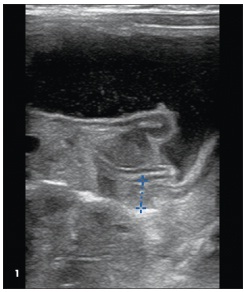

Alexander C. Arroyo, MD; Alexander K.C. Leung, MD, MBBS, FRCPC, FRCP; Kael Duprey, MD, JD; Marisa Vermeulen, DO

A 23-day-old boy born at 39 weeks’ gestation via normal spontaneous vaginal delivery was brought to the emergency department with vomiting of 1 week’s duration.